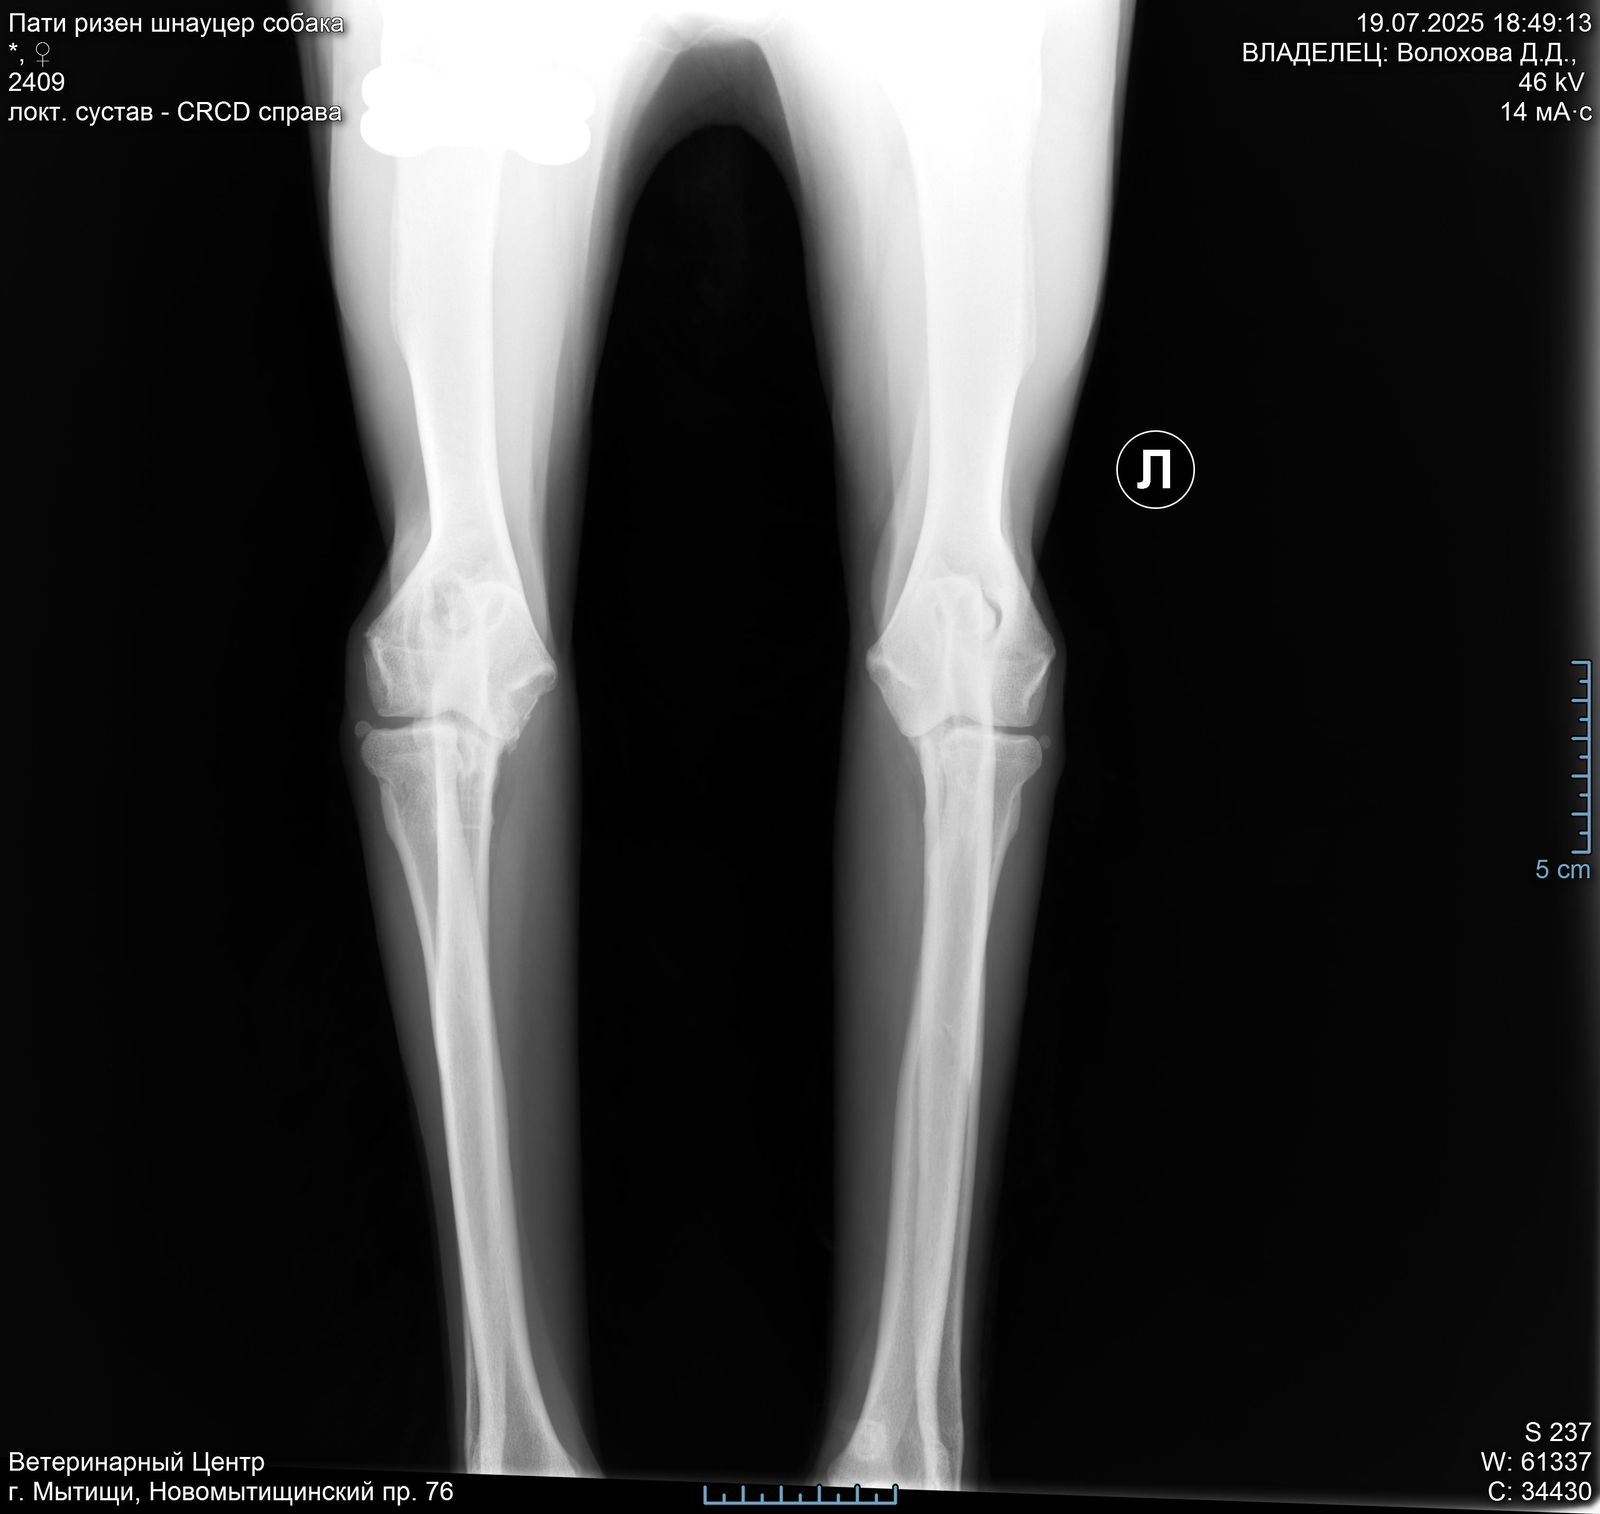

Задние ноги не идеал, но портить жизнь не должны.

Левый локтевой пока под вопросом, есть там проблемы или нет. КТ покажет.